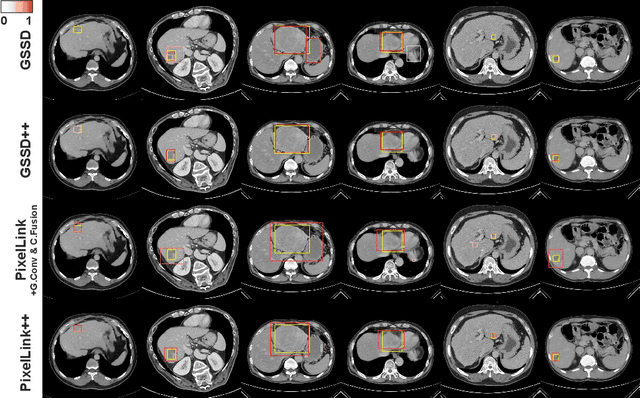

The computer-aided diagnosis of focal liver lesions (FLLs) can help improve workflow and enable correct diagnoses; FLL detection is the first step in such a computer-aided diagnosis. Despite the recent success of deep-learning-based approaches in detecting FLLs, current methods are not sufficiently robust for assessing misaligned multiphase data. By introducing an attention-guided multiphase alignment in feature space, this study presents a fully automated, end-to-end learning framework for detecting FLLs from multiphase computed tomography (CT) images. Our method is robust to misaligned multiphase images owing to its complete learning-based approach, which reduces the sensitivity of the model's performance to the quality of registration and enables a standalone deployment of the model in clinical practice. Evaluation on a large-scale dataset with 280 patients confirmed that our method outperformed previous state-of-the-art methods and significantly reduced the performance degradation for detecting FLLs using misaligned multiphase CT images. The robustness of the proposed method can enhance the clinical adoption of the deep-learning-based computer-aided detection system.